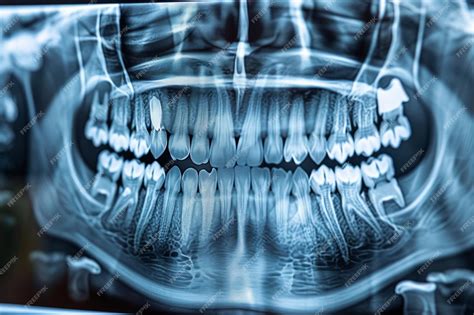

When you visit a dentist for a comprehensive oral health assessment, you might be asked to undergo a specific type of imaging known as a panoramic Xray teeth scan. Unlike standard bitewing X-rays that focus on a few teeth at a time, this diagnostic tool captures a wide-angle view of your entire mouth, including the upper and lower jaws, the temporomandibular joints (TMJ), and the surrounding bone structures. Understanding what this procedure entails can help alleviate any anxiety you might feel before your dental appointment, as it is a safe, painless, and highly efficient way for your dentist to gain a complete picture of your oral health.

The primary advantage of a panoramic X-ray is the sheer volume of information it provides in a single image. While localized dental X-rays are excellent for detecting small cavities between teeth, they often miss larger issues hiding deep within the jaw or under the gumline. A panoramic Xray teeth image serves as a baseline for your dental history and is often the first step in creating a long-term treatment plan.

Once the image is captured, it is processed digitally and appears almost instantly on the dentist's monitor. The panoramic Xray teeth view allows your dentist to zoom in and out, highlighting specific areas of interest. You might see lines or shadows that seem confusing, but your dentist will walk you through the image, pointing out the health of your bone structure and the orientation of your tooth roots. This visual aid is an excellent educational tool, as it allows you to see exactly what the dentist sees, making it easier to understand the necessity of recommended treatments.